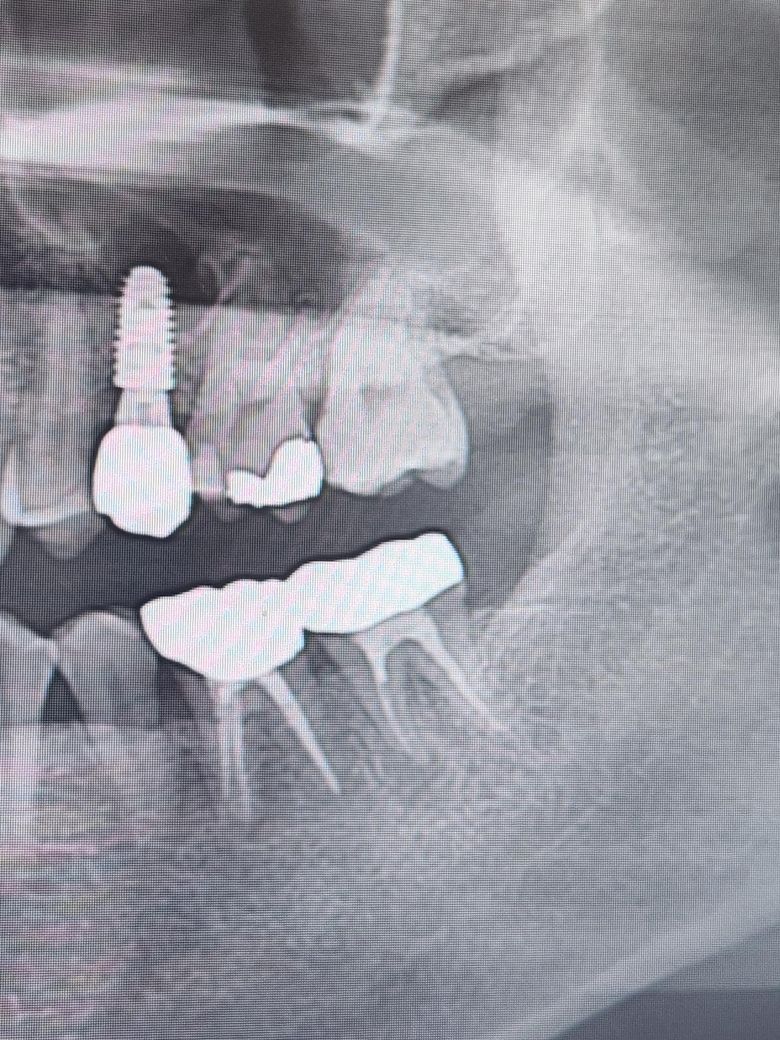

• 2번 째 사진

오른쪽 어금니의 경우 방사선상 치조골의 손실형태가 J자 형태를 보이는 전형적으로 치근파절이 생겼을때 보이는 증상입니다.

치아 뿌리에 금이 갔다면 결과적으로 발치를 하는 방법으로 치료를 하게 됩니다.

왼쪽아래 어금니의 경우에는 신경관 감염으로 인한 치근단 질환으로 재신경치료를 해서 염증을 줄이는것을 시도해 볼수 있을것으로 생각됩니다.

염증이 잡혀있긴하지만 아주 심각해서 당장 뺄 정도인지는 의문입니다 시간을 가지고 재신경치료, 치근단절제술 시도해볼만한 상황같습니다